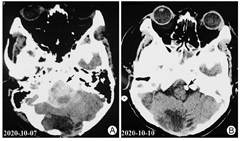

现病史:患者,男性,33岁,未婚,汉族,2021年5月9日因"吞咽困难7月余"入院。患者7月前因蛛网膜下腔出血(图1A)行左侧椎动脉瘤栓塞术,术后复查颅脑CT未见新发出血(图1B)。后因呼吸衰竭行气管切开术,经抗感染、呼吸机辅助呼吸、床边康复等治疗2个月后,拔除气切套管。后经系统康复治疗5个月仍不能经口进食,伴言语欠清、四肢活动欠灵活。

注:图1A,颅脑CT结果示蛛网膜下腔出血(箭头所示),枕骨骨质缺损。图1B,颅脑CT结果示右小脑术后改变,右枕部硬膜下积液,颅内动脉瘤栓塞术后改变(箭头所示),蛛网膜下腔出血